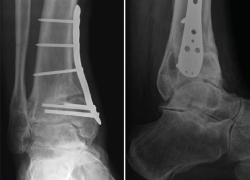

La meta de la SMOT es la reconstitución o modificación del eje del tobillo para modificar la carga articular y, de esta manera, disminuir o retrasar la progresión de la lesión al cartílago articular(15,16,17,18). Dependiendo de los grados necesarios para la corrección, la osteotomía puede ser conformada por una cuña de apertura medial (Figuras 1 y 2) o, si se requieren > 10° de corrección o una sindesmosis fusionada, una cuña de cierre lateral para evitar una discrepancia de longitud importante(19). Cualquiera que sea la técnica, suele incluirse osteotomía del peroné en ambos casos. Si el peroné tiene claramente una longitud mayor a la fisiológica, restaurar la posición neutra del astrágalo resulta imposible. Knupp et al.(20) realizaron una modificación a la clasificación de la artrosis en varo de tobillo mediante la adición de un algoritmo de tratamiento para los procedimientos extraarticulares. Esta nueva clasificación permite categorizar los distintos tipos de artrosis de tobillo en varo y facilita la decisión terapéutica, especialmente cuando una SMOT aislada resulta insuficiente. Por otra parte, se puede añadir a este procedimiento una osteotomía intraarticular (plastia de pilón tibial o plafonplastia) si se observa persistencia de la inclinación astragalina por artrosis unicompartimental (Figura 3).

Figura 1. Artrosis de tobillo en varo grado 3A de Tanaka.

Figura 2. Resultado del caso de la Figura 1 tras osteotomía supramaleolar de adición medial fijada con placa de titanio de bajo perfil (caso del Dr. Víctor Valderrábano).